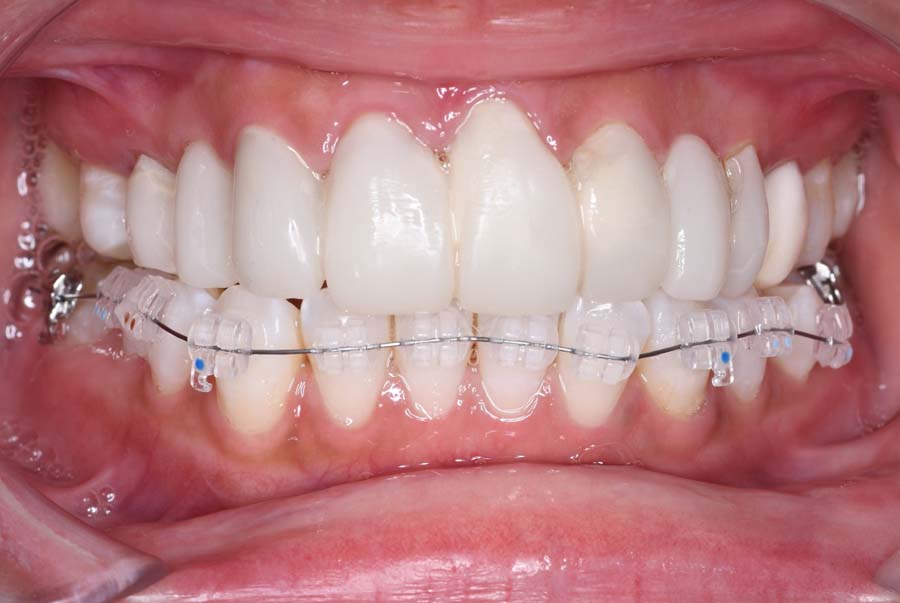

2024年 10月 下顎MTM開始

2024年 10月10日